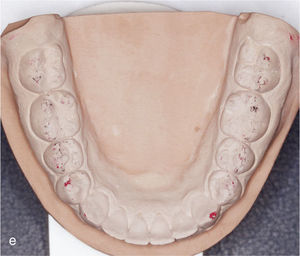

Sector anterior de la arcada inferior con dientes rotados y apiñados (a). La conformación de la arcada se realiza mediante la extracción del diente 42 y la colocación de ataches en los dientes 33 a 44. Vista intraoral de la arcada inferior con un aspecto armonioso y el espacio cerrado (b).